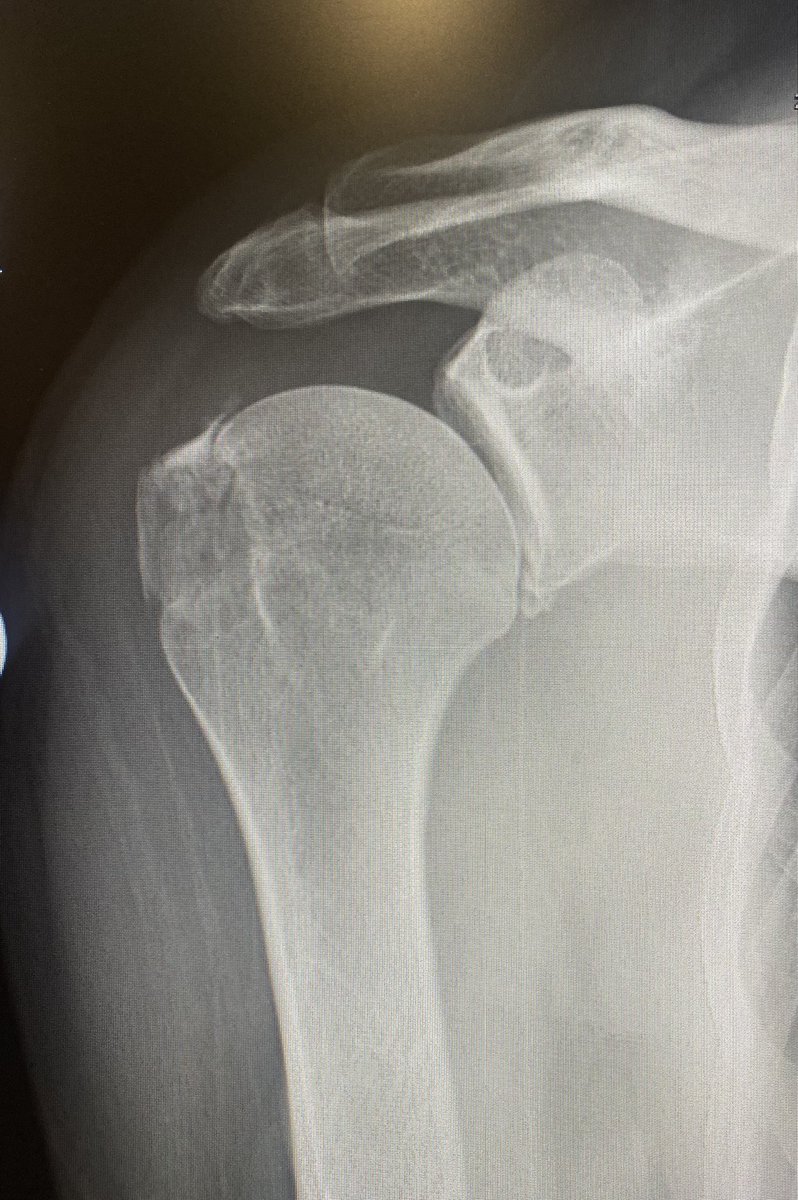

@suzy_speirs @northwoods1980 @PierreCollin Any experience with these post endoscopic calcaneoplasty and how they tend to get on?

@northwoods1980 @PierreCollin I do! They are a pain. That one is a really clear bony prominence!